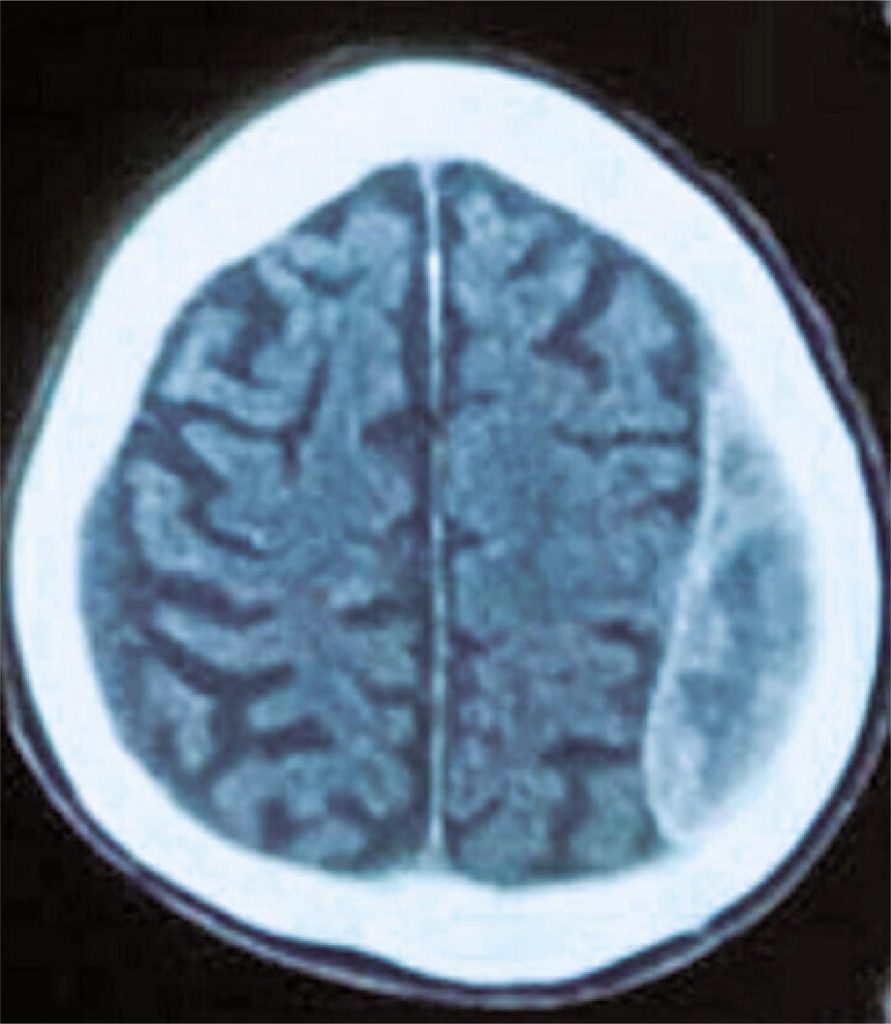

Individuals at high risk of bleeding comprise a significant portion of patients submitted to coronary angioplasty. The optimal duration of dual antiplatelet therapy for these patients remains uncertain, and the use of risk stratification scores for hemorrhagic and ischemic complications, such as PRECISE-DAPT and DAPT, help in the decision-making process. We report the case of an octogenarian patient with known high risk of bleeding (PRECISE-DAPT = 65; DAPT = 0) diagnosed with two chronic subdural hematomas, 4 weeks after angioplasty with placement of drug-eluting stent to treat coronary artery disease. Based on the latest evidence from the literature on the management of antiplatelet agents for this group of patients, the decision was for early discontinuation of clopidogrel on the 31st day after angioplasty. The clinical course was successful over 24-month follow-up.